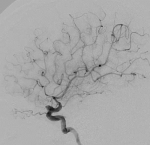

脑血管造影提示右侧颈内动脉颅内段多发动脉瘤(反主动脉弓)

脑血管造影提示右侧颈内动脉颅内段多发动脉瘤

4mm×30mm Streamline

术后4月余随访:多发动脉瘤均未见显影,远端残余轻度狭窄

术前术后对比